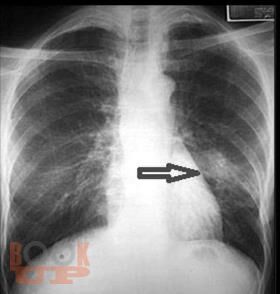

Пневмония у детей

Излагается современная информация по классификации пневмонии у детей, ее эпидемиологии, этиологии, клинических особенностях в зависимости от этиологических и анатомо-физиологических факторов и фоновых заболеваний. Значительная часть пособия посвящена диагностике, принципам современной антибактериальной терапии с последних достижений в педиатрии.